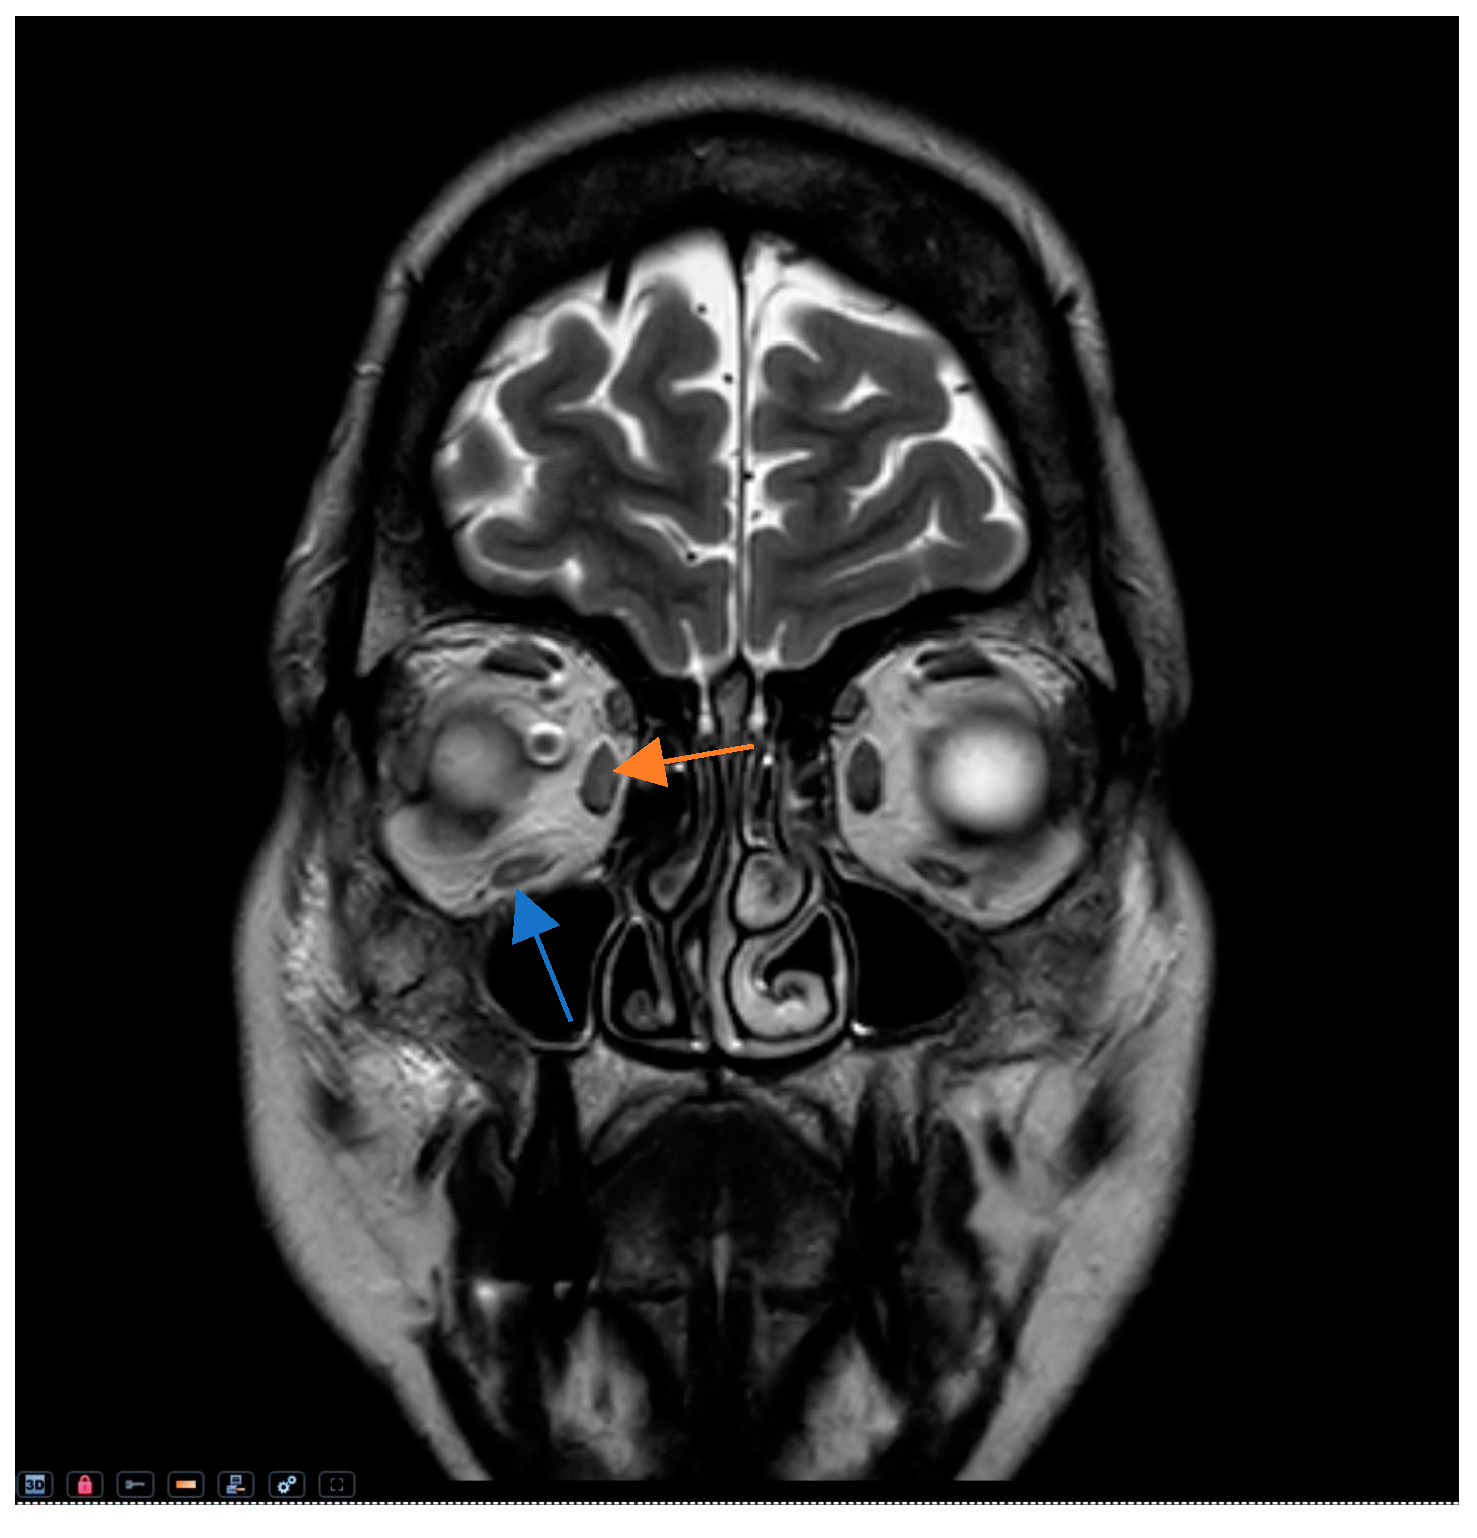

| MRI * (T2-weighted) | Hyperintense signal | Hyperintensity indicative of acute inflammation, edema, and increased fluid. |

| Gadolinium Contrast (MRI) * | Enhancement | Increased contrast enhancement indicating inflammation or venous congestion. |

| Fat-suppressed MRI (STIR) * | Enhanced signal | Clearly delineates optic nerve involvement and inflammatory changes. |